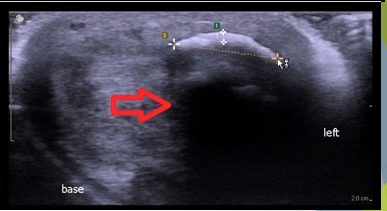

Dense calcified dorsal plaque. Red arrow indicates acoustic shadowing

Patient presenting with curvature of the erect penis and erectile dysfunction for 1 year

Transverse view: Echogenic plaque, Acoustic shadowing.

Longitudinal view: Multiple linear calcific plaques, Acoustic shadowing